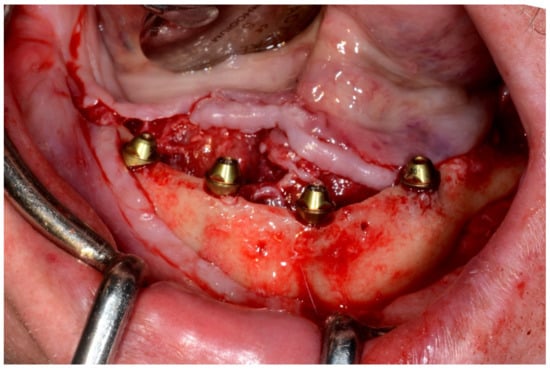

Figure 26.

Mandibular implants in place.

In August 2019, four guided dental implants were placed at sites # 34, # 31, # 41, and # 44 (Figure 35 and Figure 36).

Figure 35.

Implant bed preparation by using guided drills inserted into specific ad hoc drill handles.

Figure 36.